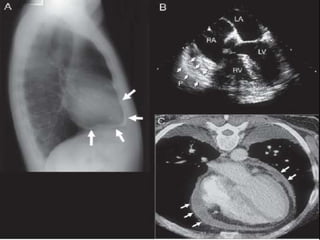

Pericarditis constrictiva

Radiografía de Torax

50% Calcificaciones

50% derrame pleural

Tomografía Computada

Métodos de Imagen

La apariencia normal del pericardio en la TAC y/o la RMI

no excluye el diagnóstico

Un pericardio engrosado en la TAC y/o la RMI

no es sinónimo por sí mismo

de Pericarditis Constrictiva

Pericarditis Constrictiva Engrosamiento Pericárdico ECO transtorácico Detecta pericardio > 5 mm ETE Sensibilidad 95% Pericardio > 3 mm Especificidad 86% TAC y RMI son la elección No diferencia fibrosis de calcificación Constricción con Pericardio no engrosado en 18%

Pericarditis constrictiva Radiografía de Torax 50% Calcificaciones 50% derrame pleural

Pericarditis constrictiva Tomografía Computada